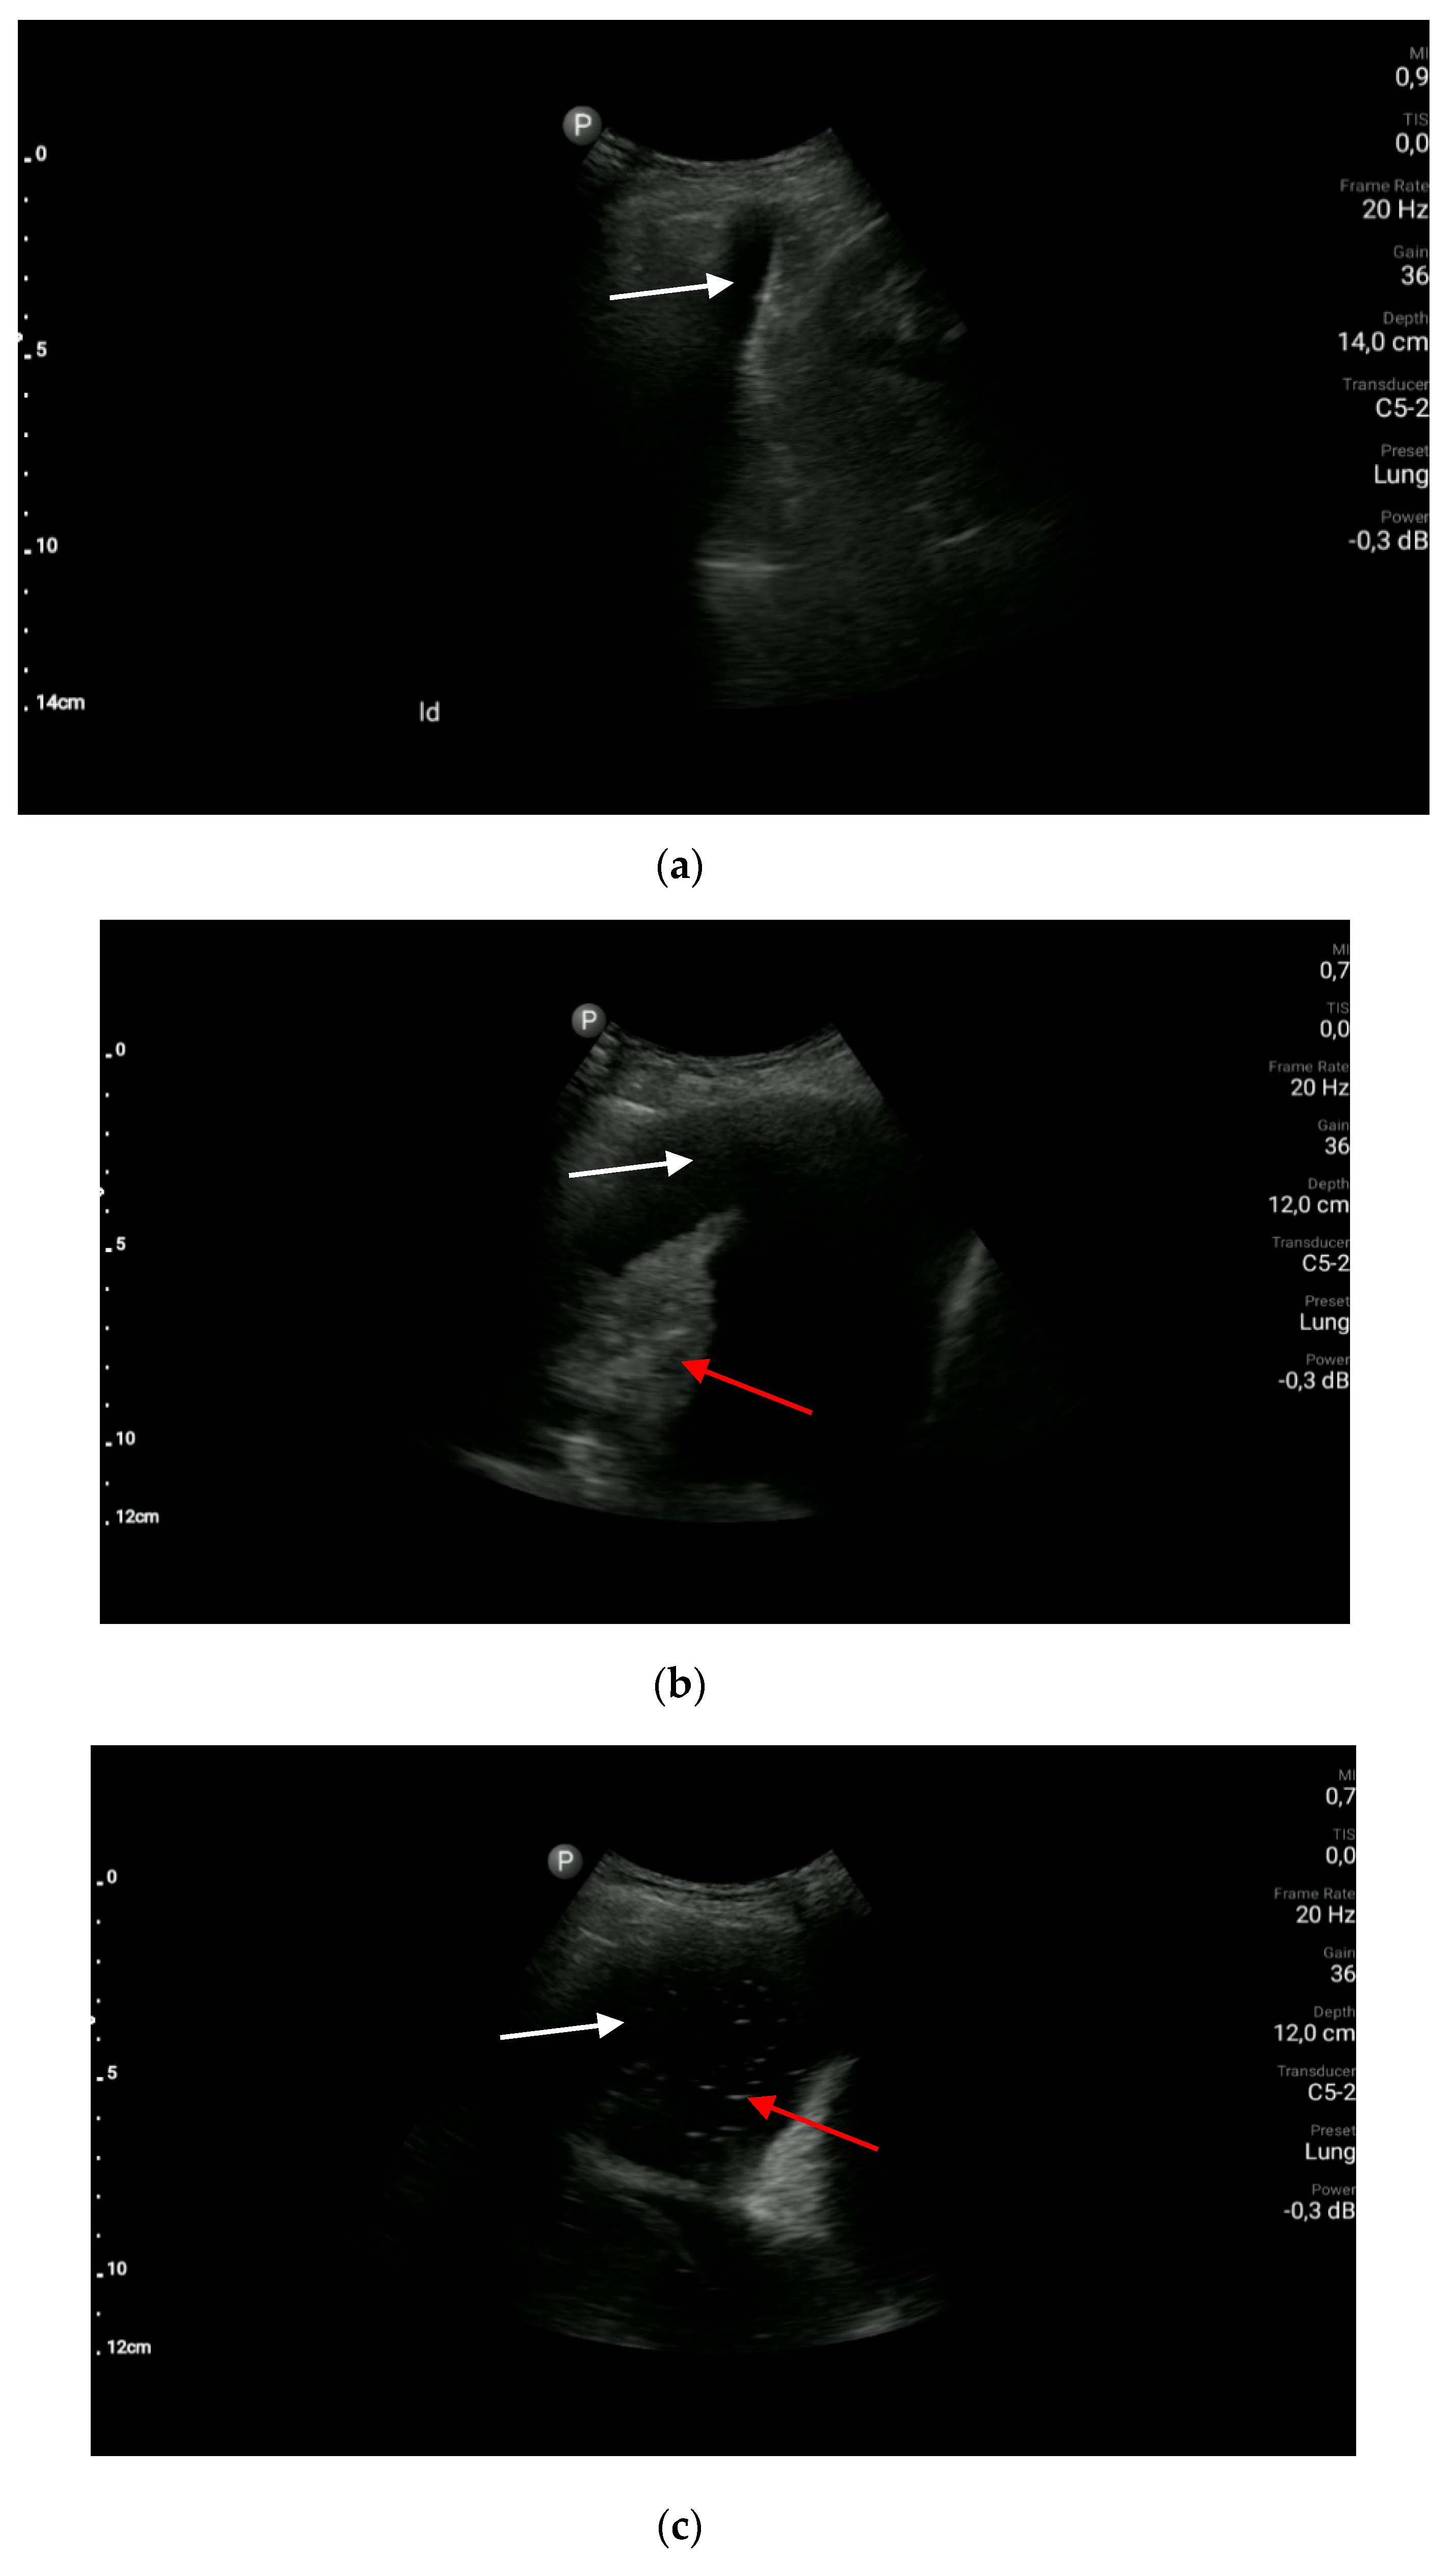

Pneumonia

- The sonographic features of pneumonia are as follows: consolidation, irregular marginal contour, air bronchogram, the air trapping sign, comet-tail artifacts (B-lines), normal vascular pattern in CD and PD (color Doppler and power Doppler) options, and the presence of pleural effusion. (A1)

- Inflammatory lesions are categorized as parenchymatous (consolidation with an irregular marginal contour, dynamic air bronchogram visible within the consolidation and/or the air trapping sign), vascular (normal flow pattern in CD and PD options) and pleural (pleural effusion). This description of lesions does not apply to bronchopneumonia.

- Consolidation means an airless area of the lung.

- An air bronchogram is the air visible in the bronchial tree within the consolidation.

- A dynamic air bronchogram is visible on inspiration and disappears on expiration.

Atelectasis

- The sonographic features of compression atelectasis are as follows: pleural effusion, consolidation of a homogeneous echogenicity and echostructure, static air bronchogram, the air trapping sign, and normal vascular pattern in CD and PD options. (A1)

- The sonographic features of resorption atelectasis are as follows: consolidation of a homogeneous echogenicity and echostructure, fluid bronchogram, static air bronchogram, normal vascular pattern in CD and PD options, and possible visualization of a pathological mass at the top of the consolidation. (A1)

- The sonographic features of pulmonary embolism may be as follows: consolidation, mostly wedge-shaped or oval/rounded, centrally located echo, flow amputation in the CD option (the so-called vascular sign), local fluid immediately above the subpleural lesion, and local interstitial lesions. (A1)